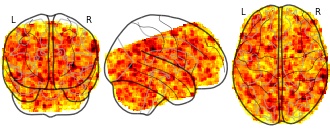

EmailClick to copy linkLink copied Cite(2018). Sliding-window analysis tracks fluctuations in amygdala functional connectivity associated with physiological arousal and vigilance during fear conditioning: windowed right amygdala tstat [Dataset]. http://identifiers.org/neurovault.image:43172niftiAvailable download formatsUnique identifierhttps://identifiers.org/neurovault.image:43172Dataset updatedJun 30, 2018License

Cite(2018). Sliding-window analysis tracks fluctuations in amygdala functional connectivity associated with physiological arousal and vigilance during fear conditioning: windowed right amygdala tstat [Dataset]. http://identifiers.org/neurovault.image:43172niftiAvailable download formatsUnique identifierhttps://identifiers.org/neurovault.image:43172Dataset updatedJun 30, 2018LicenseCC0 1.0 Universal Public Domain Dedicationhttps://creativecommons.org/publicdomain/zero/1.0/

License information was derived automaticallyDescriptionFSL5.0

Collection description

We evaluated whether sliding-window analysis can reveal functionally relevant brain network dynamics during a well-established fear conditioning paradigm. To this end, we tested if fMRI fluctuations in amygdala functional connectivity (FC) can be related to task-induced changes in physiological arousal and vigilance, as reflected in the skin conductance level (SCL). Thirty-two healthy individuals participated in the study. For the sliding-window analysis we used windows that were shifted by one volume at a time. Amygdala FC was calculated for each of these windows. Simultaneously acquired SCL time series were averaged over time frames that corresponded to the sliding-window FC analysis, which were subsequently associated with the whole-brain seed-based amygdala sliding-window FC using the GLM. Surrogate time series were generated to test whether connectivity dynamics could have occurred by chance. In addition, results were contrasted against static amygdala FC and sliding-window FC of the primary visual cortex, which was chosen as a control seed, while a physio-physiological interaction (PPI) was performed as cross-validation. During periods of increased SCL, the left amygdala became more strongly coupled with the bilateral insula and medial prefrontal cortex, core areas of the salience network. The sliding-window analysis yielded a connectivity pattern that was unlikely to have occurred by chance, was spatially distinct from static amygdala FC and from sliding-window FC of the primary visual cortex, but was highly comparable to that of the PPI analysis. We conclude that sliding-window analysis can reveal functionally relevant fluctuations in connectivity in the context of an externally cued task.

Subject species

homo sapiens

Modality

fMRI-BOLD

Analysis level

group

Cognitive paradigm (task)

pavlovian conditioning task

Map type

T